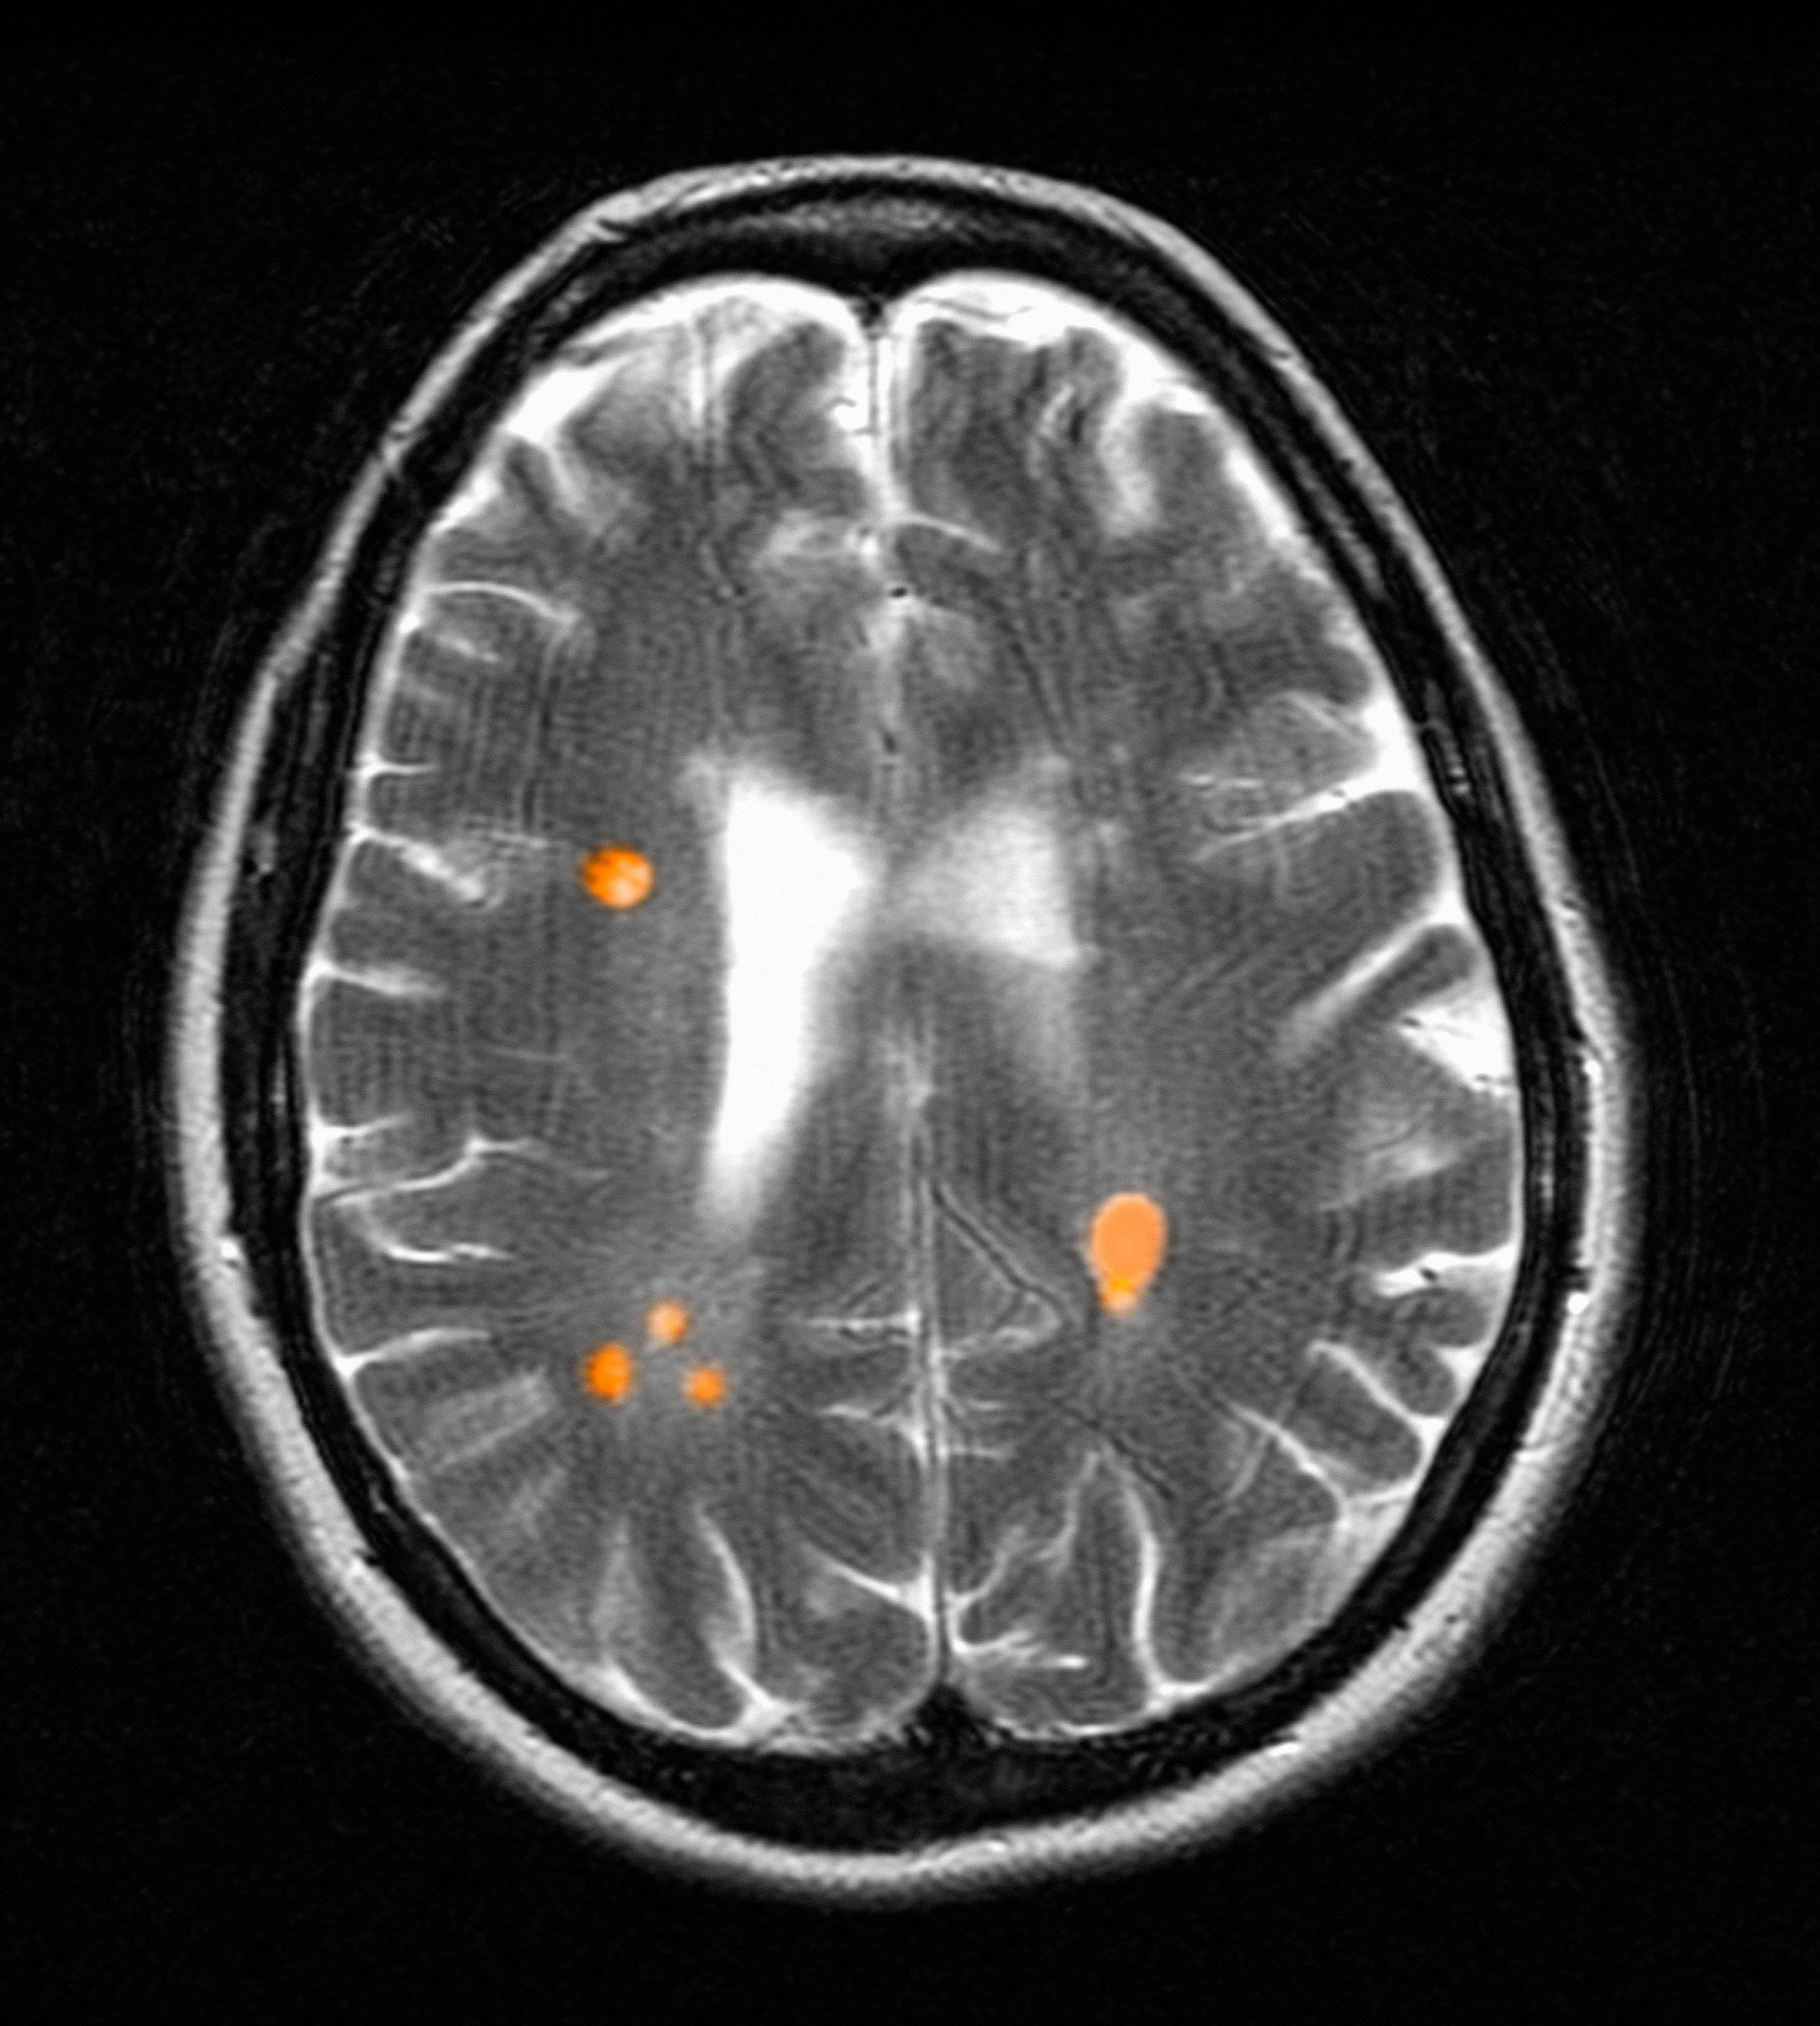

Chronic active lesions (CALs) are an important driver of PIRA. When an acute gadolinium-enhancing lesion develops in PwMS, there are 3 possible fates of this lesion. The lesion may become chronically inactive, remyelinate, or transition to CALs.14 The histopathologic signature of CALs is compartmentalized, low-grade inflammation behind an intact blood-brain barrier with evidence of both active and chronic components.15 CALs may be found not only in cerebral white matter but also in the cerebral cortex and spinal cord.16,17 Combined MRI and histopathological studies have shown that iron-laden microglia/macrophages can be detected by susceptibility-based MRI as a rim of paramagnetic signal surrounding select T2-lesions.19 These PRLs represent an in vivo imaging biomarker of CAL (Figure 1C). According to the North American Imaging in MS Cooperative (NAIMS) consensus criteria, a PRL must surround at least two-thirds of the outer edge of a T2-lesion, be visible in ≥ 2 consecutive MRI slices, and cannot be contrast enhancing.20